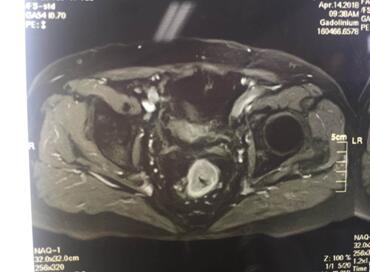

入院后譚曙光主任帶領(lǐng)賀賽奇副主任、周高副主任醫(yī)師及周平主治醫(yī)師等科室業(yè)務(wù)骨干為汪老制定詳細(xì)診療計劃。術(shù)前盆腔MRI及腸鏡、病理診斷考慮低位直腸腺癌(T3aN0M0)。鑒于汪老年老體弱,病變位置低,基礎(chǔ)疾病多,耐受力較差,譚主任及其手術(shù)團(tuán)隊精益求精,不斷完善診療措施,術(shù)前采取MDT(多學(xué)科合作)模式,于4月18日在全麻腹腔鏡下行直腸癌根治術(shù)+D3淋巴結(jié)清掃術(shù)+粘連松解,手術(shù)順利,術(shù)中徹底松解腹腔內(nèi)粘連,標(biāo)準(zhǔn)的TME(直腸全系膜切除)及D3淋巴結(jié)清掃,腹腔鏡下吻合口加固縫合,手術(shù)出血僅30ml,在原有的手術(shù)切口處取出手術(shù)標(biāo)本。